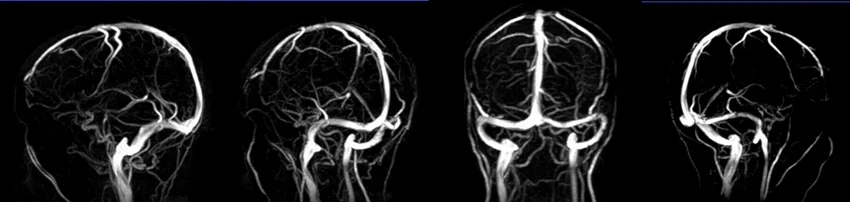

MRV brain phase contrast(PC) 3D images

Post processed MIP images from 3D rowdata